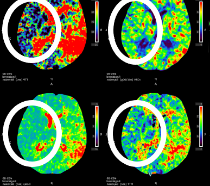

頭蓋内動脈狭窄症

左側の中大動脈が狭窄しており、血流が滞っています。

この状態を放置すると脳梗塞を発症するリスクがあります。

頭蓋内動脈狭窄症(MRA)

頭蓋内動脈狭窄症(CTP)